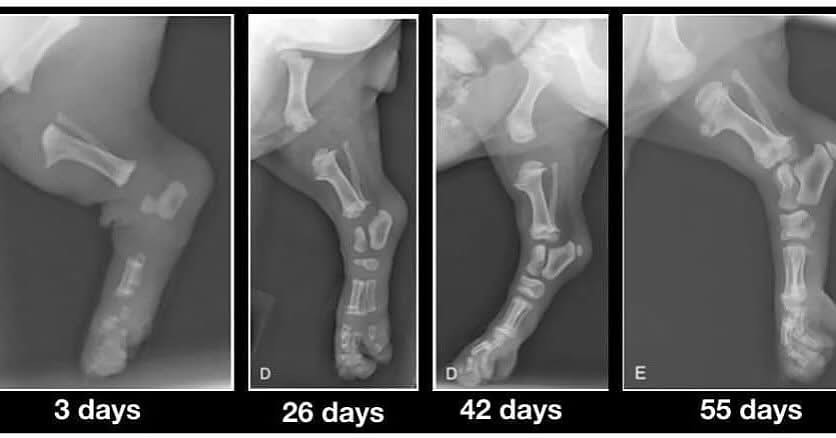

Ich greife dieses Thema auf, weil ich ein sehr ausdruckstarkes Röntgenbild im Internet gefunden habe, wo die Knochen von Welpen verschiedenen Alters dargestellt werden. Hier kann man sehr gut sehen, wie die Knochenbildung voranschreitet. Es sieht so aus, als ob die Knochenteile ohne Verbindung miteinander sind, doch die Gelenkknorpel sieht man auf den Röntgenbildern nicht. Diese sogenannten Wachstumsfugen ( Epiphysenfugen ) sind noch nicht geschlossen und die Gelenkköpfe sind sehr weich und empfindlich! Das Knochenwachstum wird durch sogenannte Osteoblasten, die für das Einlagern von Calziumphosphat verantwortlich sind. Soweit zum Längenwachstum; die Knochendicke erfolgt durch Anlagerung.